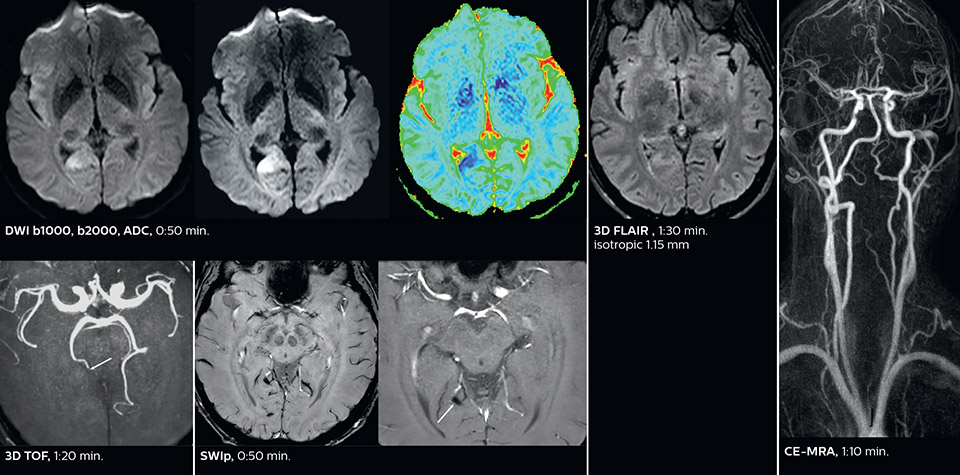

The ability to perform more sequences can help in making a swift and confident diagnosis. “For example, our stroke cases usually include the regular sequences that every center does (b1000 diffusion, FLAIR, time-of-flight angiography), but we also image supra aortic vessels, and we can replace a gradient echo sequence with a fast 50-second susceptibility-weighted sequence, and all of this doesn’t add much time. because all the regular sequences are accelerated on Elition.”

“The time savings with Compressed SENSE and MultiBand SENSE make it easier to add sequences to give us additional insights. Depending on the context and the first results, we might add a DSC perfusion to assess the ischemic penumbra, an ASL perfusion to help find an alternative cause in case of normal diffusion, or add a high-resolution T1 sequence for a stroke patient, to quickly assess wall imaging in emergency cases. The additional sequences can help improve patient management, because we can already consider some alternative diagnoses if the morphological MRI is normal.”

Using MultiBand SENSE allowed the staff to improve their diffusion quality. “Our diffusion sequence was already fast before, about 40 seconds. Now with Elition, it still lasts 40 seconds, but we improved the spatial resolution by 0.2 mm and use high b-values to be more sensitive to visualize changes related to acute stroke,” says Dr. Savatovsky.

Fast acute stroke protocol

This is an example of acute ischemic stroke with distal occlusion of the right posterior cerebral artery. Note the improved visibility of the ischemic territory on the diffusion weighted image with high b-value. The 3D FLAIR shows a distal PCA occlusion. The fast SWIp depicts the thrombus on the isolated second echo image. The total scan time (including SmartBrain, preparations and a fast 3D T1w TSE Gd) is 8:00 minutes.